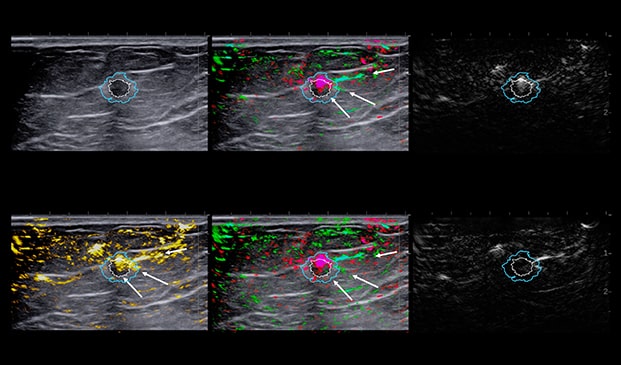

Case Example 2:

48-year-old female, presented with an abnormal mammogram/tomo. 1.9 cm mass seen on ultrasound, negative doppler.

Case Example 2: Observations

Deoxygenated hemoglobin internal to the mass is represented by intense disorganized or polymorphic pink colorization seen on the 6-up image.

These are typical malignant characteristics on OA which are represented on the combined map (upper middle), total hemoglobin (lower left) and relative map (lower middle).

Invasive Ductal Carcinoma Grade III

- ER-

- HER2-

- PR-

- Ki67=80%

The Mass was up-classified to BI-RADS 4C. Biopsy confirmed triple negative cancer. TNC masses typically present with intense deoxygenated mainly internal vessels. Masses with high Ki67 tend to have a lot of internal vessels mainly in the internal and boundary zones, unless there is necrosis.